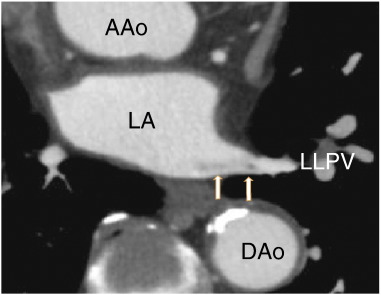

The patient was a 78-year-old male who presented with chest pain and had no previous treatment with warfarin. D-dimer was less than 0.5 μg/ml (normal value < 1.0 μg/ml), protein S activity was 91% (normal range 60–150%), and protein C activity was 66% (normal range 64–146%). He was treated with aspirin (82 mg i.d.) as an antiplatelet therapy. The patient was referred to our hospital for the evaluation of coronary artery stenosis. The chest roentgenogram was negative for lung cancer. The patient had no symptoms of cough, cerebral infarction or cancer, and the patient had no history of either catheter ablation or lung surgery. A 64-MDCT scan showed a pulmonary vein thrombus (Fig. 1); however, there were no thrombi in the left lower pulmonary vein (LLPV) at first. A non-contrast enhanced vessel, which might have been completely occluded, approached from the upper side (Fig. 2A). There, a non-contrasted branch of the pulmonary vein at the upper side of the LLPV was observed (Fig. 2B), which extended proximally in keeping the position on the upper side of LLPV (Fig. 2C). The contrast enhancement defects did not diffuse and enter the LA (Fig. 2D).

Axial images showing the left lower pulmonary vein thrombus (arrows). AA; ...

Fig. 1.

Axial images showing the left lower pulmonary vein thrombus (arrows). AA; ascending aorta, DAo; descending aorta, LA; left atrium, LLPV; left lower pulmonary vein.